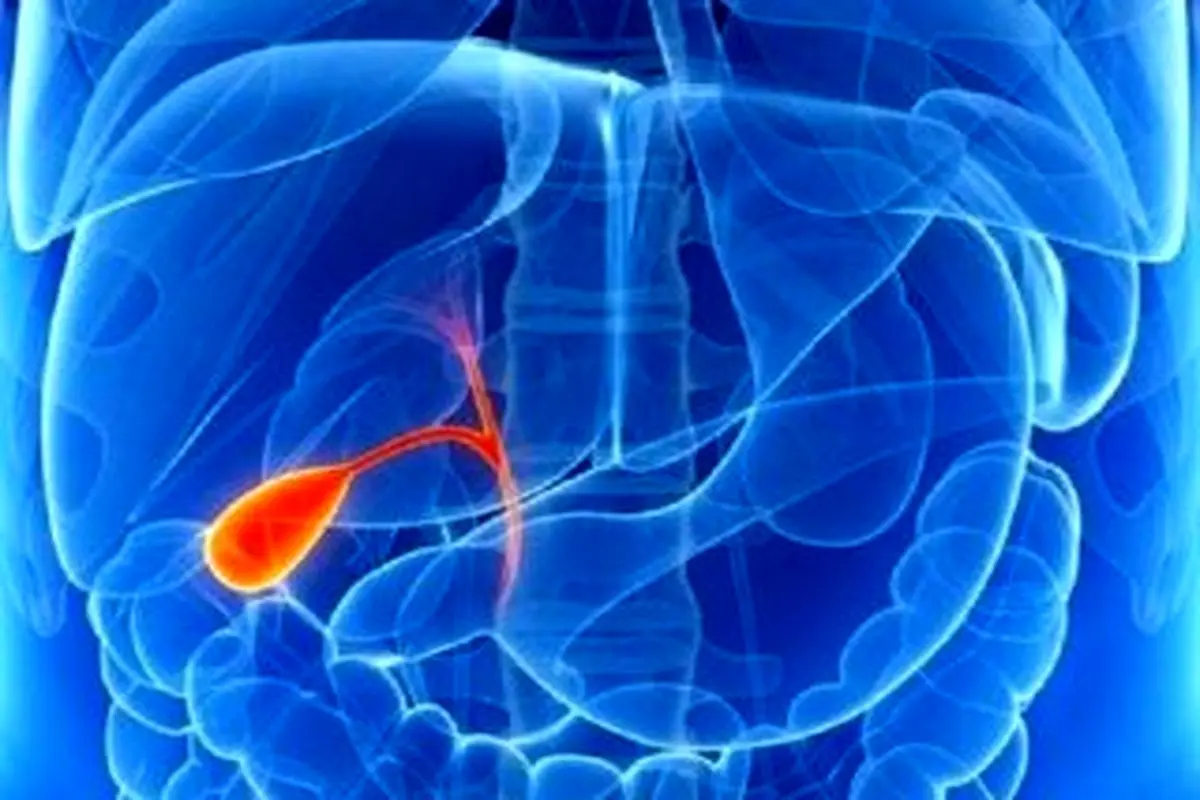

چه کسانی مبتلا به سنگ صفرا میشوند؟

پارسینه: فوق تخصص گوارش به تشریح علل ابتلا به سنگ صفرا پرداخت و گفت: سنگ کیسه صفرا در خانمهای چاق و چند قلوزا شایعتر است.

ناصر ابراهیمی فوق تخصص گوارش، با بیان اینکه سنگ کیسه صفرا در خانمهای چاق و چند قلوزا شایعتر است، گفت: سنگهای صفرا بیشتر در افراد بالای ۴۰ سال دیده میشود.

وی با بیان اینکه افزایش چربی خون به ویژه تری گلیسرید بالا یکی از عوامل ابتلا به سنگ کیسه صفرا است، افزود: افرادی که دیابت دارند مستعد ابتلا به سنگ کیسه صفرا هستند.

این فوق تخصص گوارش با تاکید بر اینکه مصرف قرصهای ضد بارداری که پروژسترون بالایی در بدن تولید میکنند با ایجاد وقفه در انقباضهای کیسه صفرا بر تشکیل این نوع سنگها تاثیر دارند، تصریح کرد: در افراد کم تحرک و همچنین کسانی که عمل جراحی چاقی انجام داده اند سنگ کیسه صفرا بیشتر دیده میشود.

ابراهیمی با بیان اینکه افراد قطع نخاعی در معرض ابتلا به سنگ صفرا هستند، گفت: مسئله وراثت نیز در ابتلا به سنگ صفرا دخیل است.

وی با تاکید بر اینکه استفاده از برخی داروها نیز در ابتلا به سنگ صفرا نقش دارد، افزود: داروهایی که برای کاهش چربی خون استفاده میشود و برخی از آنتی بیوتیکها در ایجاد سنگ کیسه صفرا نقش دارند.

ابراهیمی با بیان اینکه گرسنگیهای طولانی نیز میتواند به تشکیل سنگ در کیسه صفرا کمک کند، گفت: در حاملگی به علت افزایش تولید هورمون پروژسترون انقباضهای کیسه صفرا کاهش یافته و فرد مستعد ابتلا به سنگ کیسه صفرا میشود.

وی با بیان اینکه افزایش چربی خون به ویژه تری گلیسرید بالا یکی از عوامل ابتلا به سنگ کیسه صفرا است، افزود: افرادی که دیابت دارند مستعد ابتلا به سنگ کیسه صفرا هستند.

این فوق تخصص گوارش با تاکید بر اینکه مصرف قرصهای ضد بارداری که پروژسترون بالایی در بدن تولید میکنند با ایجاد وقفه در انقباضهای کیسه صفرا بر تشکیل این نوع سنگها تاثیر دارند، تصریح کرد: در افراد کم تحرک و همچنین کسانی که عمل جراحی چاقی انجام داده اند سنگ کیسه صفرا بیشتر دیده میشود.

ابراهیمی با بیان اینکه افراد قطع نخاعی در معرض ابتلا به سنگ صفرا هستند، گفت: مسئله وراثت نیز در ابتلا به سنگ صفرا دخیل است.

وی با تاکید بر اینکه استفاده از برخی داروها نیز در ابتلا به سنگ صفرا نقش دارد، افزود: داروهایی که برای کاهش چربی خون استفاده میشود و برخی از آنتی بیوتیکها در ایجاد سنگ کیسه صفرا نقش دارند.

ابراهیمی با بیان اینکه گرسنگیهای طولانی نیز میتواند به تشکیل سنگ در کیسه صفرا کمک کند، گفت: در حاملگی به علت افزایش تولید هورمون پروژسترون انقباضهای کیسه صفرا کاهش یافته و فرد مستعد ابتلا به سنگ کیسه صفرا میشود.